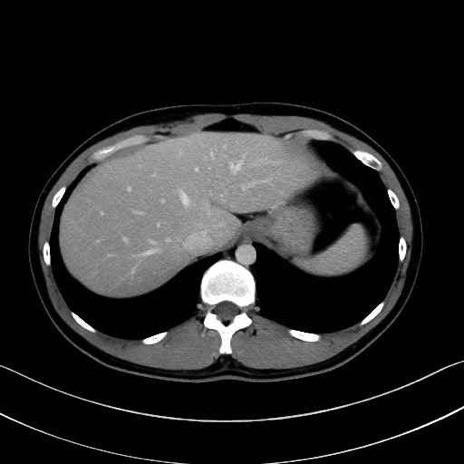

【症例】20歳代 男性 スクリーニング

■起始:典型的には腹腔動脈幹(celiac trunk)から左胃動脈・総肝動脈とともに三分岐し、脾動脈は左後上方へ向かう。

■走行:膵上縁または膵実質背側を蛇行しながら左方へ進み、膵尾部近傍で脾門へ至る。蛇行の程度は個体差が大きい。

■終枝:脾門部で複数の終末枝に分かれ、上極・下極枝や脾門枝群を形成する。胃短動脈群や左胃大網動脈はしばしば脾動脈から分岐する。